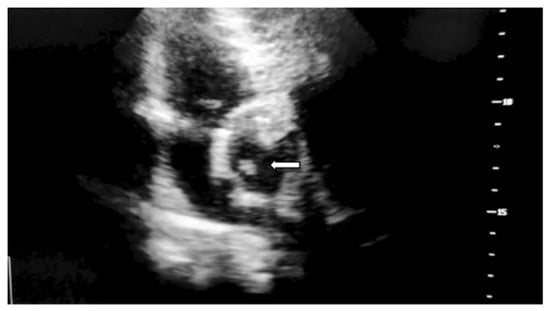

Fungal endocarditis, despite being a rare diagnosis, has a higher morbidity and mortality rate compared to bacterial endocarditis. Candida species are the most common isolated pathogens involved in fungal endocarditis. Diagnosis is suspected in patients with underlying conditions such as cancer, myelodysplastic syndrome, diabetes, or intravascular catheters, where the modified Duke criteria apply. Management of the patient requires a multidisciplinary team (cardiologist, infectious diseases consultant, cardiac surgeon) along with antifungal treatment. We present the case of a 60-year-old male with biological prosthetic aortic valve replacement in the previous year for bicuspid aortic stenosis, admitted for a 5-day history of fever, nausea and minor urinary symptoms. The blood cultures were positive for Candida parapsilosis. Transthoracic cardiac ultrasound revealed a hypoechogenic mass attached to the aortic valve at the prosthetic fixation site. Although diagnosis was rapidly confirmed and treatment was administered shortly after first suspected, the patient developed, at first, cavernous sinus thrombosis and, later, fatal ST elevation myocardial infarction. The patient died despite efficient antifungal therapy, initially with Anidulafungin in monotherapy and later in combination with Fluconazole. The reported case emphasizes the importance of managing fungal endocarditis, the need for urgent diagnostic attention and multidisciplinary team approach by infectious diseases specialist, cardiologist, neurologist and heart surgeon.

Figure 1